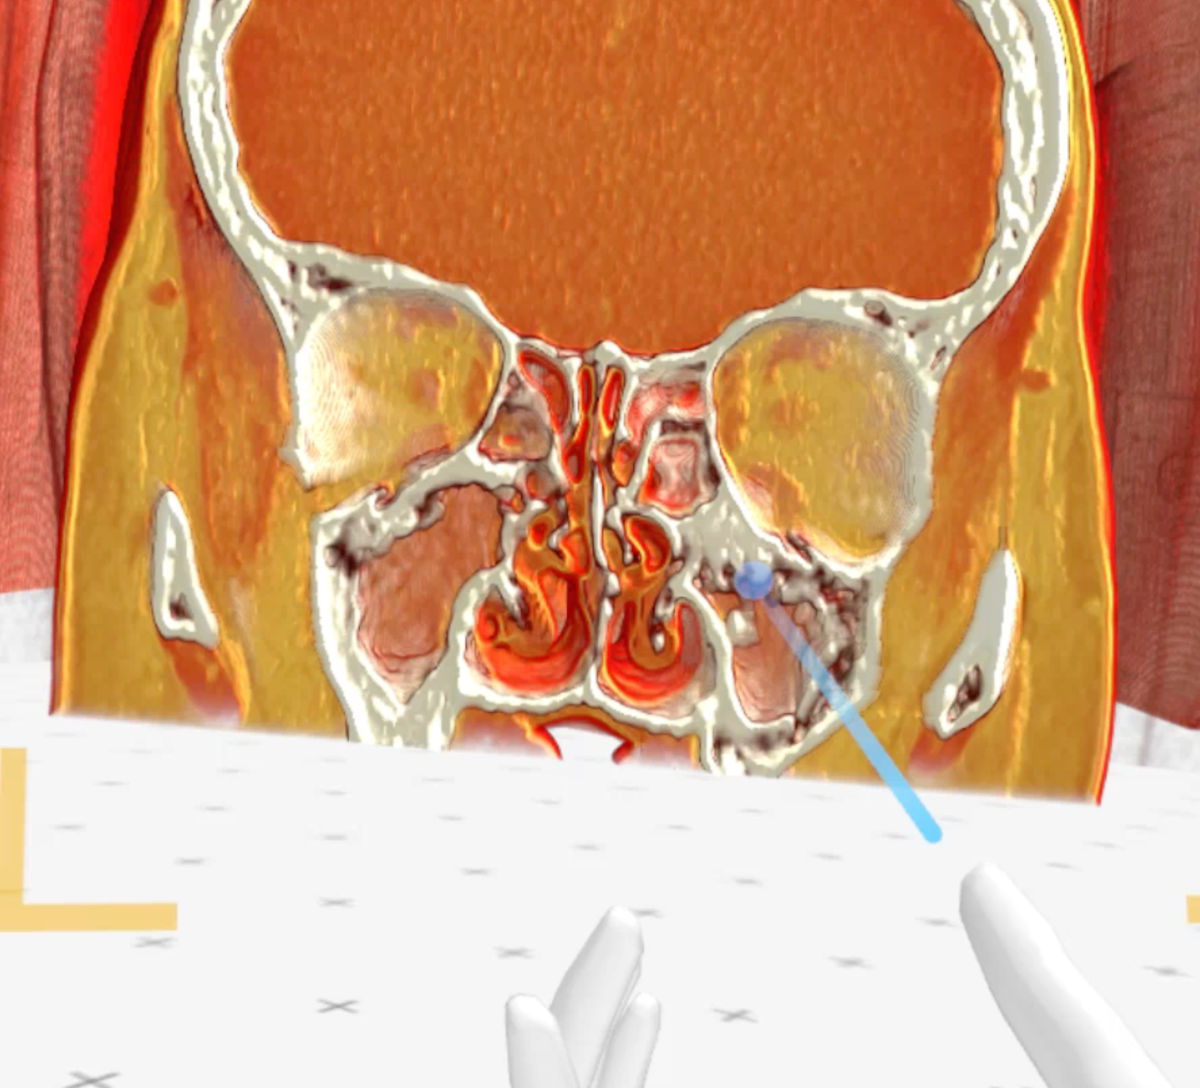

CT and MRI scans showed no aeration of the paranasal sinuses, foci of bone destruction and a significant amount of scar tissue. The anatomy of the nasal cavity was completely disturbed (Fig. 4-5).

Figure 4. Axial CT scan shows residual aeration of the right maxillary sinus (blue arrow), bone destruction and no aeration of the left maxillary sinus (red arrow), and destruction of the nasal septum (yellow arrow).

Figure 5. Coronal CT scan shows no aeration of the paranasal sinuses and deformation of the nasal cavity anatomy.